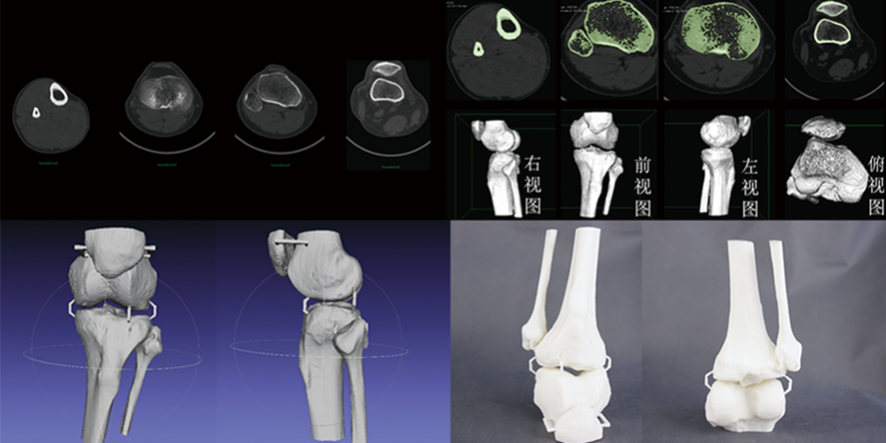

隨著醫(yī)學(xué)技術(shù)的飛速發(fā)展,3D打印骨骼和CT數(shù)據(jù)三維建模技術(shù)逐漸應(yīng)用于骨科手術(shù)中,為骨科手術(shù)醫(yī)生提供了新的解決方案。本文將介紹這些技術(shù)如何幫助醫(yī)生提高手術(shù)準(zhǔn)確性、降低手術(shù)風(fēng)險(xiǎn)和縮短康復(fù)周期,以及如何獲取相關(guān)學(xué)習(xí)資源和培訓(xùn)途徑。

3D打印骨骼和CT數(shù)據(jù)三維建模技術(shù)能夠生成精確的患者解剖結(jié)構(gòu)模型,幫助醫(yī)生更清晰地了解骨折或畸形的詳細(xì)情況。在手術(shù)前,醫(yī)生可以利用這些模型制定個(gè)性化的手術(shù)方案,確保手術(shù)過程中的精確操作。

通過手術(shù)前的模擬和手術(shù)計(jì)劃制定,醫(yī)生可以提前預(yù)演各種可能的手術(shù)步驟和方案,從而降低手術(shù)過程中的不確定性和風(fēng)險(xiǎn)。此外,3D打印的患者特定導(dǎo)板和植入物也有助于提高手術(shù)安全性。

應(yīng)用3D打印骨骼和CT數(shù)據(jù)三維建模技術(shù)的手術(shù)通常具有較高的精確性,有助于減少手術(shù)創(chuàng)傷和術(shù)后并發(fā)癥。這意味著患者的康復(fù)時(shí)間可能會(huì)相對縮短,使他們更快地恢復(fù)正常生活。